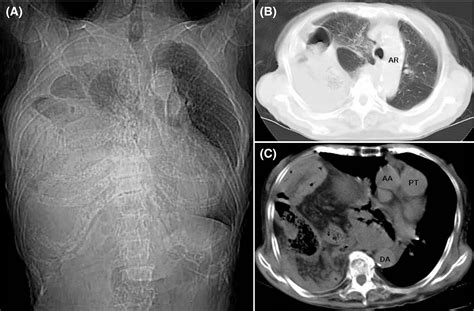

CT Scan: Offers detailed images of the chest and abdomen, helping to identify the location and size of the hernia.